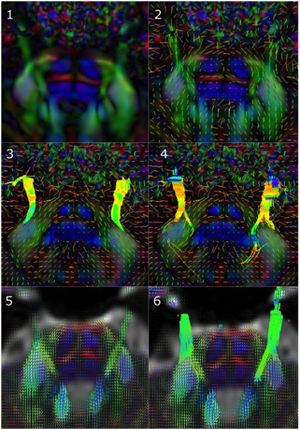

Improvement of Pyramidal Tract Side Effect Prediction using a Data-Driven Method in Subthalamic Stimulation

Publication: IEEE Trans Biomed Eng. 2017 Sep;64(9):2134-41. PMID: 27959795 Authors: Baumgarten C, Zhao Y, Sauleau P, Malrain C, Jannin P, Haegelen C. Institution: Signal and Image Processing Laboratory, Department LTSI , University of Rennes, France. Abstract: Objective: Subthalamic nucleus deep brain stimulation (STN DBS) is limited by the occurrence of a pyramidal tract side effect (PTSE) induced by electrical activation of the pyramidal tract. Predictive models are needed to assist the surgeon during the electrode trajectory preplanning. The objective of the study was to compare two methods of PTSE prediction based on clinical assessment of PTSE induced by STN DBS in patients with Parkinson's disease. Methods: Two clinicians assessed PTSE postoperatively in 20 patients implanted for at least three months in the STN. The resulting dataset of electroclinical tests was used to evaluate two methods of PTSE prediction. The first method was based on the volume of tissue activated (VTA) modeling and the second one was a data-driven-based method named Pyramidal tract side effect Model based on Artificial Neural network (PyMAN) developed in our laboratory. This method was based on the nonlinear correlation between the PTSE current threshold and the 3-D electrode coordinates. PTSE prediction from both methods was compared using Mann-Whitney U test. Results: 1696 electroclinical tests were used to design and compare the two methods. Sensitivity, specificity, positive- and negative-predictive values were significantly higher with the PyMAN method than with the VTA-based method (P < 0.05). Conclusion: The PyMAN method was more effective than the VTA-based method to predict PTSE. Significance: This data-driven tool could help the neurosurgeon in predicting adverse side effects induced by DBS during the electrode trajectory preplanning. |

Pre-operative registration between the ParkMedAtlis atlas and the patient’s T1 and T2 weighted MRI. Top left: axial view; top right: antero-superior left three-dimensional view of the cerebral sulci and the segmented basal ganglia, down left; parasagittal view; down right: coronal view. The red dot and line are the preplanned trajectory few days before the surgery to implant an electrode in the left subthalamic nucleus. A: anterior; P: posterior; L: left; R: right; S: superior; I: inferior. Amygdala (light pink), hippocampus (dark pink), putamen (violet), medial pallidum (orange), lateral pallidum (green), caudate nucleus (light blue), thalami (yellow), substantia nigra (grey), subthalamic nucleus (light orange), red nucleus (red), ventricles (dark blue). |